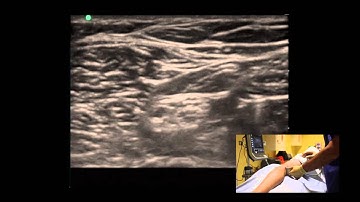

Lateral sciatic nerve block